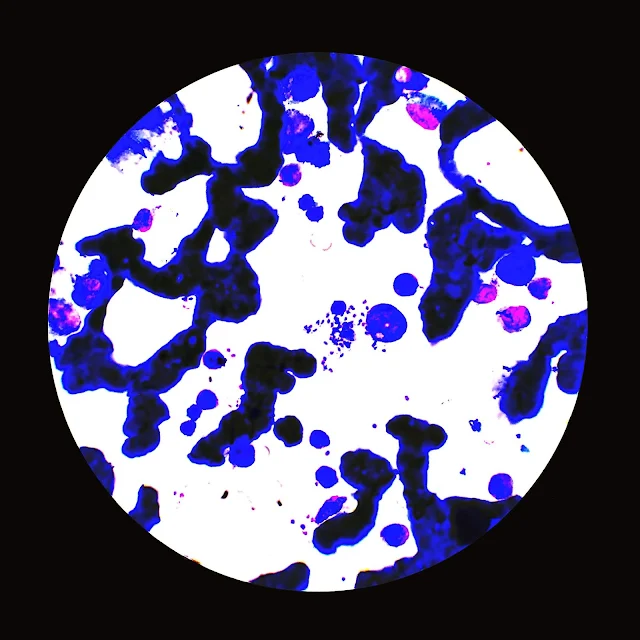

- Size and Shape: Leishmania donovani bodies are typically small, measuring 2 to 4 micrometers in length. They have an elongated oval or rod-shaped morphology.

- Internal Structures: Within the cytoplasm of the parasite, various structures can be observed, including the nucleus (kinetoplast), flagellum, and other organelles such as the mitochondrion and Golgi apparatus.

- Diagnosis of visceral leishmaniasis is typically made by detecting Leishmania donovani bodies in tissue aspirates, such as bone marrow, spleen, or lymph nodes, using microscopy.